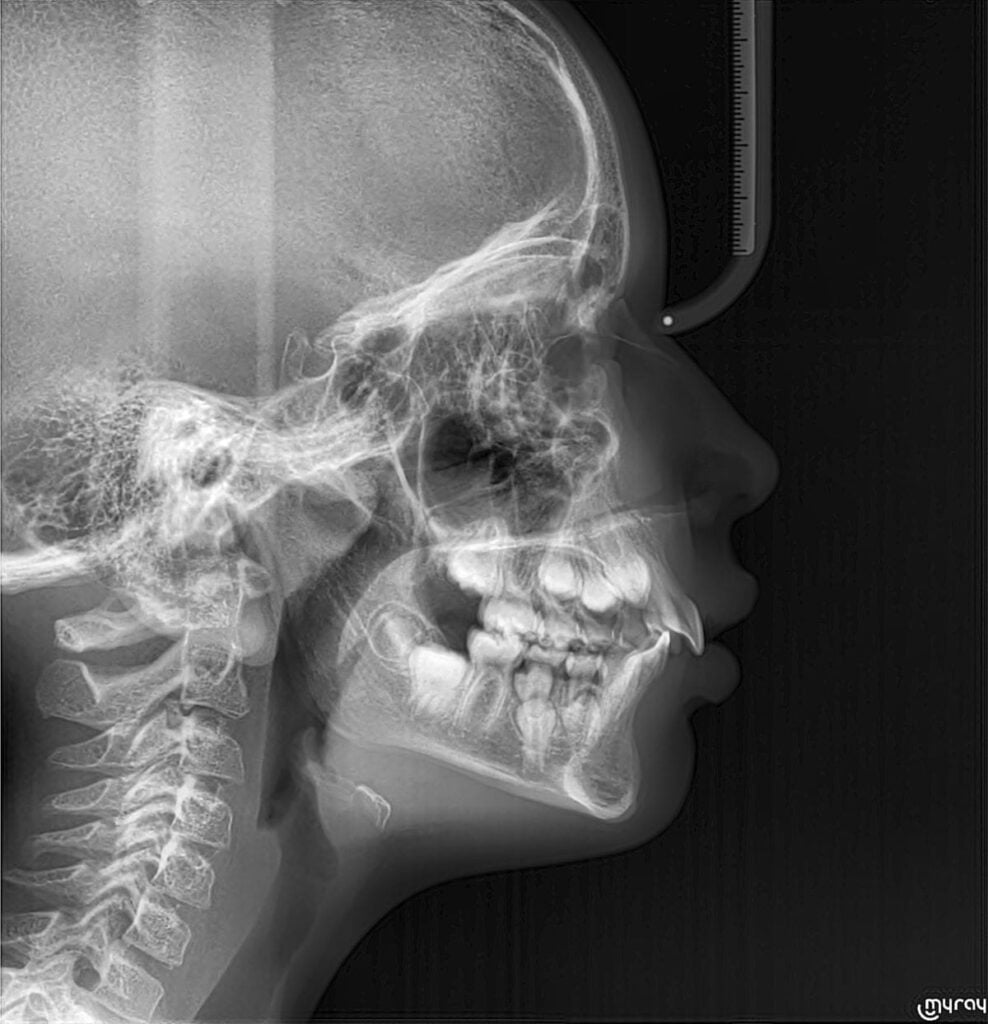

Le Dr Audrey BAEUMLIN vous recevra lors d’un premier rendez-vous pour échanger sur votre demande de traitement. Afin de vous présenter les différentes possibilités de traitement et appareillages, des radiographies et un examen clinique approfondi seront réalisés lors de cette consultation. La nécessité et la faisabilité d’un traitement orthodontique seront évaluées selon les dysmorphoses à corriger. Pour les enfants, le Dr Audrey BAEUMLIN vous expliquera le moment idéal de traitement selon la croissance des mâchoires et l’évolution des dents.

L’orthodontie va permettre d’obtenir un alignement des dents permanentes et un emboitement idéal entre les dents du haut et les dents du bas, c’est ce que l’on appelle l’occlusion dentaire. L’objectif est d’obtenir un sourire esthétique et fonctionnel au sein d’un visage équilibré et harmonieux.L’adolescence est l’étape de la vie la plus appropriée pour entreprendre la plupart des corrections orthodontiques globales. Cette période est le moment où la dentition définitive s’établit, tout en ayant un potentiel de croissance qui peut s’avérer primordial pour corriger certains déséquilibres affectant les mâchoires. Lorsqu’en effet ce décalage est trop important, il peut nécessiter une opération de chirurgie orthognatique réalisée par un chirurgien maxillo-facial sous anesthésie générale.